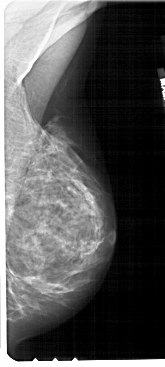

A_1724_1.RIGHT_CC

RIGHT_CC LINES 4906 PIXELS_PER_LINE 2281 BITS_PER_PIXEL 12 RESOLUTION 43.5 NON_OVERLAY